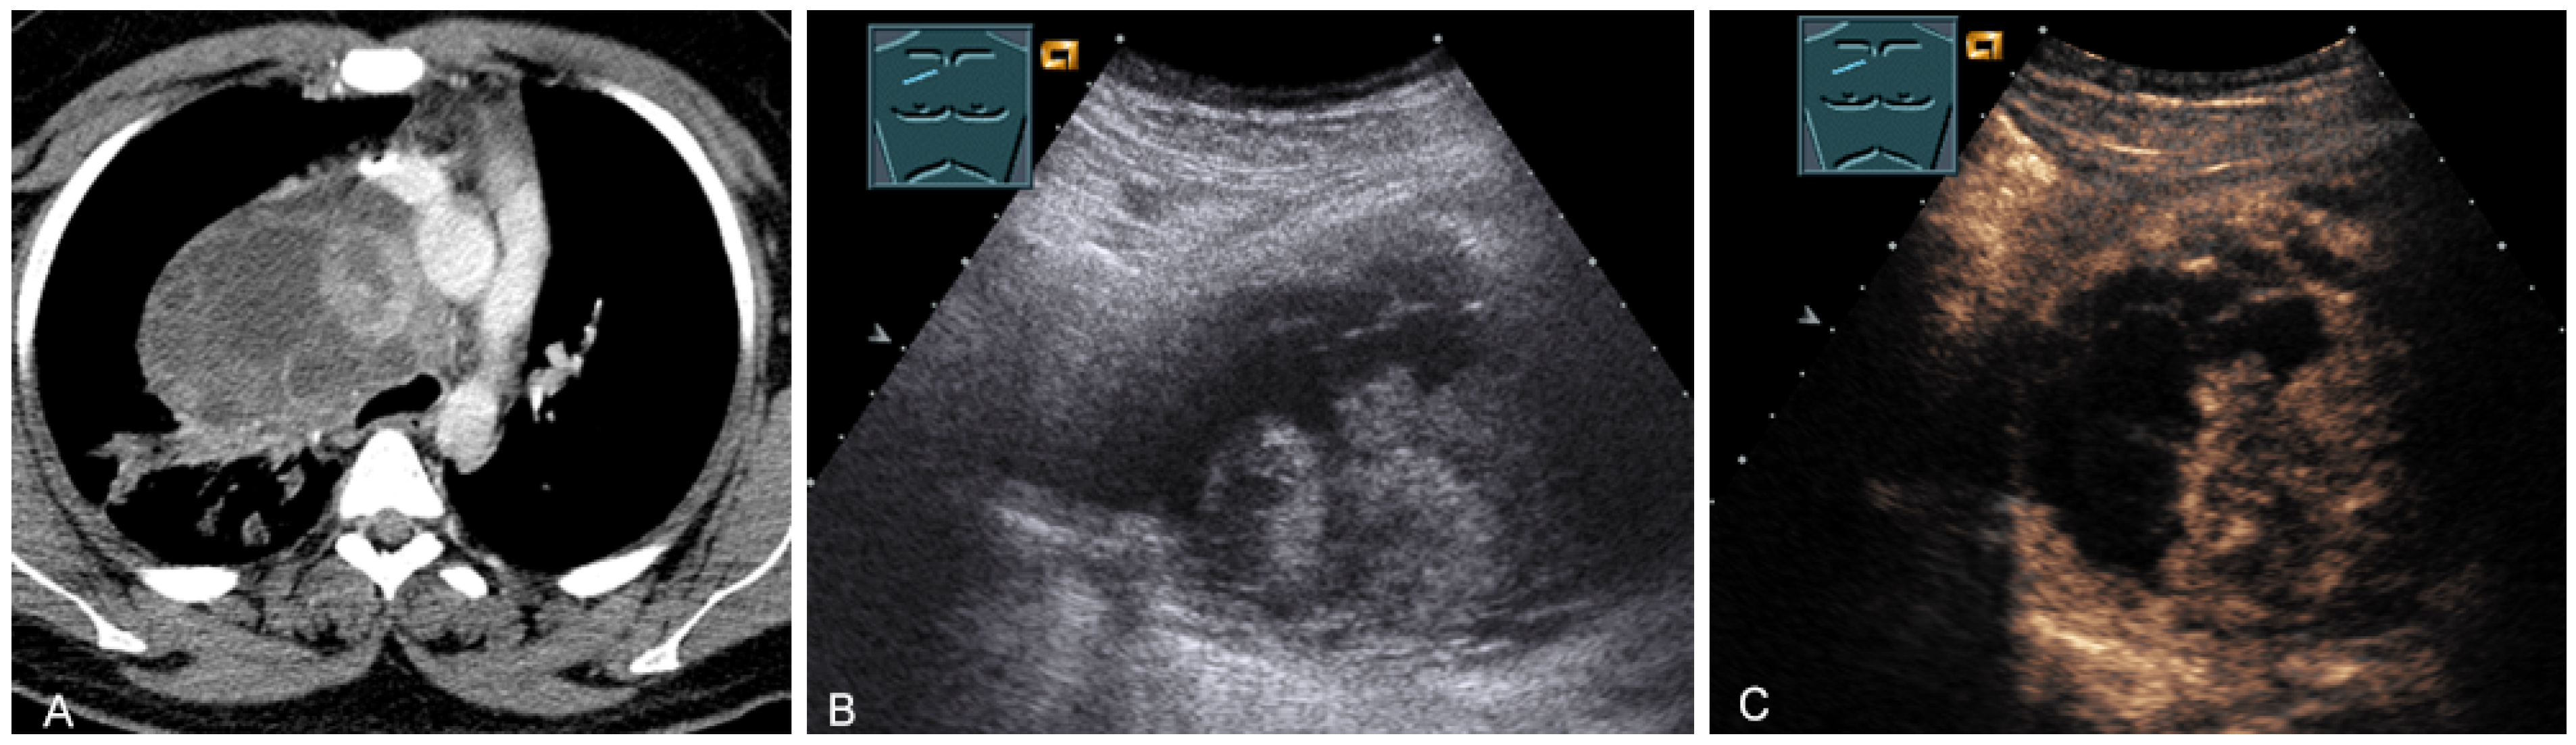

Figure 16.

A young patient with tumor formation in the paravertebral mediastinum on CT (provided by Prof. Dr. Andreas H. Mahnken, Marburg, Germany) (A), B-mode US (B), and CEUS (C), surgically confirmed as ganglioneuroma.